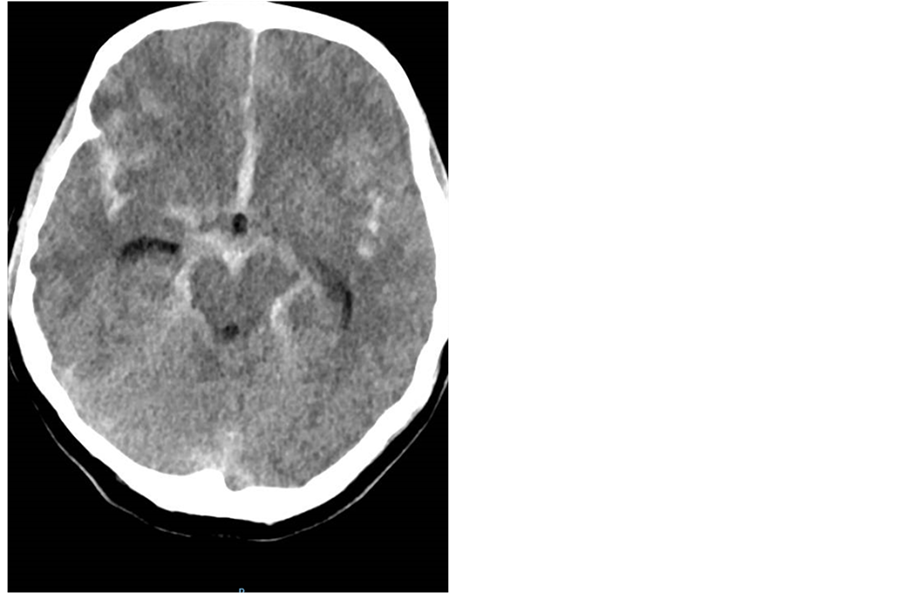

A 41-year-old, 6 months post partum woman with no past medical, presented unresponsive due to a subarachnoid hemorrhage (SAH) [Figure 3].

Figure 3. Head CT showing diffuse SAH with hydrocephalus.

Norepinephrine was started and an EVD (extra ventricular drain) was emergently placed. She had her right P-com aneurysm coiled, after which she woke up and was able to follow simple commands. She had elevated troponins due to catecholamine-related cardiac injury superimposed on possible postpartum cardiomyopathy. Her 2DECHO showed diminished EF of 35% - 40% with anteroseptal wall akinesis as well as inferolateral and basal segment wall hypokinesis. She developed pulmonary neurogenic edema. On day four she developed delayed cerebral ischemia (DCI) and milrinone was started. In spite of her receiving norepinephrine, she became hypotensive and tachycardic up to 160 BPM and vasopressin had to be added to two currently infusing pressors. The patient remained in severe vasospasm with deterioration in mental status in spite of euvolemia and blood pressure augmentation. She underwent an emergent cerebral angiogram to treat cerebral vasospasm with I.A. verapamil, but during the procedure became acutely hypotensive and eventually was pronounced brain dead.